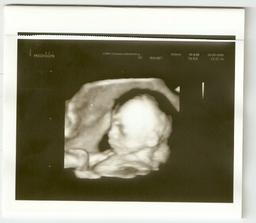

3. září - 4D Utz za námi (Sam váží 484g), byl to neskutečný zážitek se na chvíli podívat za Samem do jeho světa, musím na to pořád koukat (dostali jsme i DVD záznam). Je to nádherný chlapeček (znovu potvrzen), trošku stydlín, ale máš být po kom, že Samíku? 😉 Má krásnou tvářičku, ručičky, prstíky, nožky, ouška.., nosánek bude spíše po mámě, jsem moc pyšná! Už se ho nemůžu dočkat...